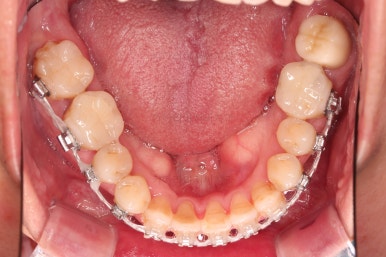

초기 단계의 주안점은 아랫니와 악궁과 어울리는 윗니 악궁의 형태를 만들어 주는 것이고요.

악궁확장장치를 사용하지 않은만큼 철사의 형태를 잘 잡아가면서 악궁 형태를 개선시킵니다.

교정 10개월째인데, 악궁형태 많이 좋아졌고, 가지런한 느낌도 많이 좋아졌습니다.

최종적으로 교합과 현실성 있는 목표를 다시 점검하고요.

예후가 불투명했던 대문니 2개를 살려 쓸 수 있는지, 교정 종료 전에 빼고 보철로 해결해야 하는지 최종평가를 하게 됩니다.

뼈가 좋지 못하고, 장기적으로 사용하기에는 한계가 있어 보이지만 유지철사로 단단히 엮어놓고 본인도 조심히 사용하신다면 당장은 발치하지 말고 최대한 오래 써보자고 결론을 냈습니다.